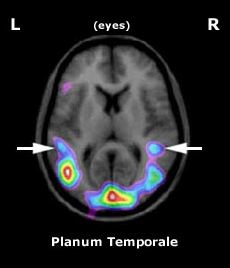

planum

Brain Wiring for Human Language, Scientific American 6/12/2000

By Kristin Leutwyler

Source: LAURA ANN PETITTO

Scientists have long been interested how the deaf process signed languages in the brain. Understanding that activity could shed light on whether the brain harbors specialized structures for decoding linguistic patterns in general¿regardless of how they are conveyed. In fact, a new study published in Tuesday’s issue of the Proceedings of the National Academy of Science suggests that the brain does have such wiring, challenging the idea that speech and sound are vital for human language. Laura Ann Petitto and Robert Zatorre of McGill University and their colleagues base their conclusions on a series of experiments using positron emission tomography (PET) brain scans of 11 profoundly deaf people and 10 hearing people.